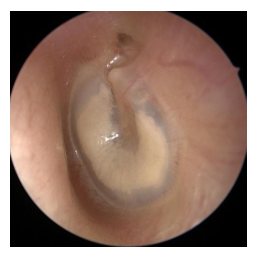

tympanosclerosis

white calcified plaques of connected tissue at TM or head of malleus